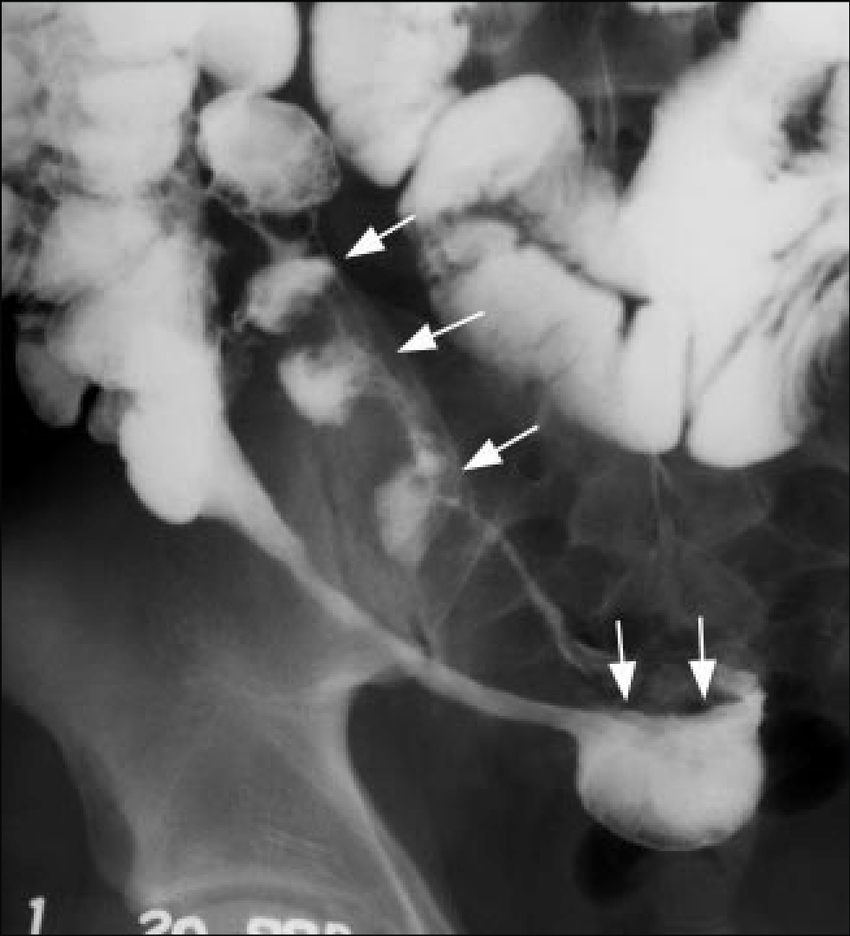

Abdome: cólon e reto

A

Esquerdo; direito.

Diverticulose cólica (seta reta). Hipertrofia da camada muscular (seta curva)